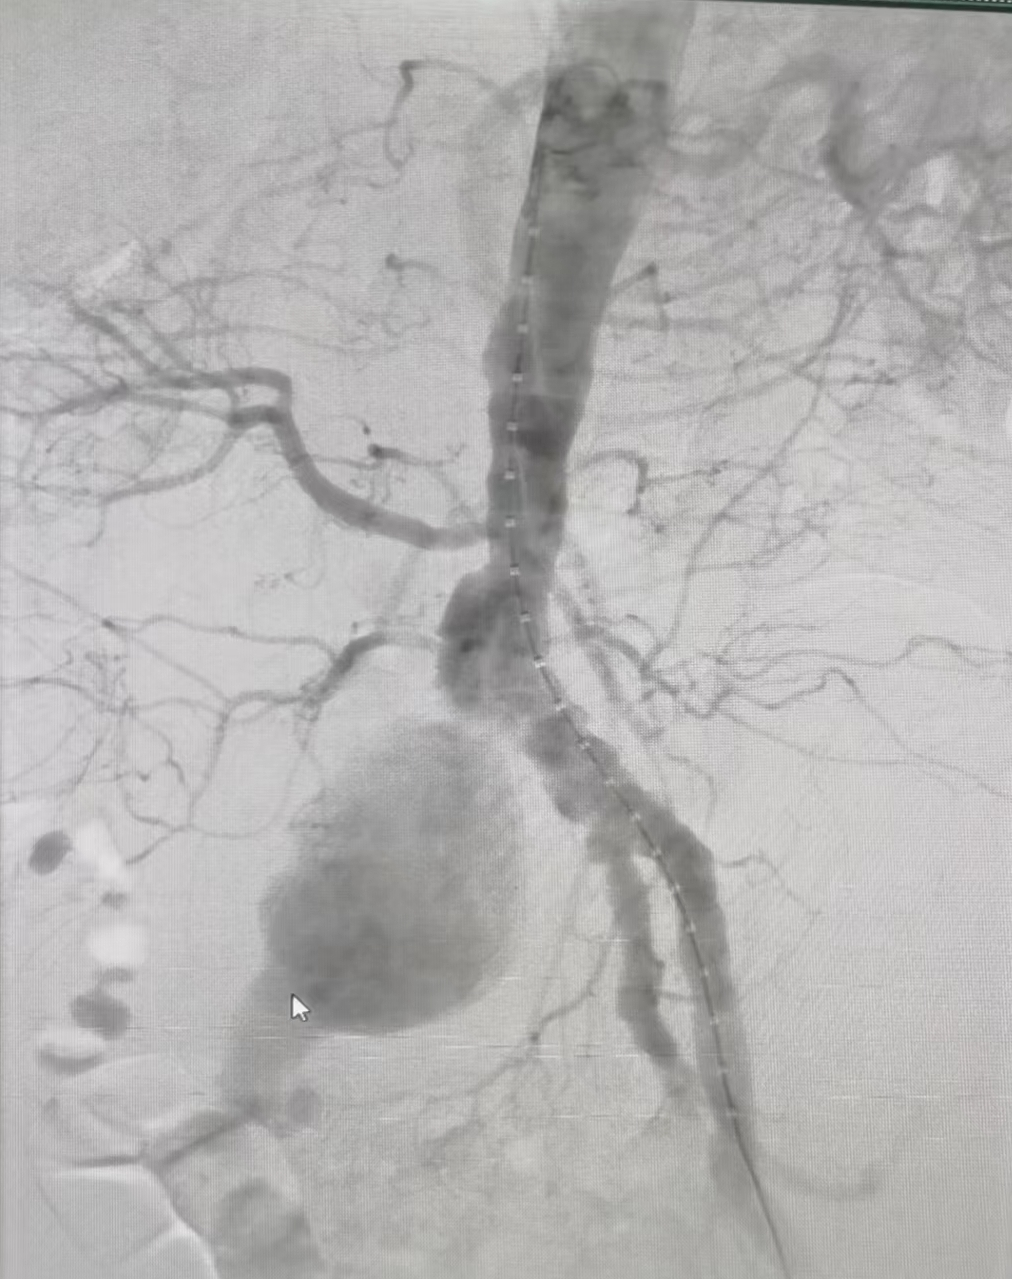

(左)腹主动脉支架置入前,(右)腹主动脉支架置入后

因患者为超高龄患者,且基础疾病多,血管病变中髂动脉瘤超大,胆囊巨大,两个病变都随时存在破馈风险,情况万分危急,患者命悬一线。急诊科迅速启动全院多学科大会诊,深夜共同讨论具体救治方案。副主任医师刘炼指出患者虽超高龄,但平时状态较好,且目前髂动脉瘤直径超过8cm,随时存在破溃风险,经逐级上报血管外科主任姚凯后,指示患者诊断明确,病情危重,需行急诊手术。经与患者及家属详细沟通并征得同意后,各学科通力合作,心内科、急诊科精准控制血压,麻醉手术科评估患者身体情况拟定麻醉方案,保障术中安全,超声科及影像科精确解析病变血管解剖结构及血管内病变性质,为血管腔内微创治疗提供有力支持,复合手术室极速完成行术前准备...微创手术腹主动脉、髂动脉覆膜支架腔内隔绝手术手术随即在周六的凌晨2时紧急开展,姚凯主任、王征副主任医师组成的专业血管疾病团队,克服患者超高龄、基础情况差等种种不利因素,成功克服全身多处血管钙化,主动脉狭窄、髂血管极度扭曲等困难,不到2小时就成功实施微创血管介入手术,术后患者平稳送入ICU病房。

中南大学湘雅三医院血管外科主任姚凯介绍主动脉瘤并非肿瘤,而是一种动脉扩张性疾病,是指由于动脉粥样硬化、炎症、感染、遗传等因素导致腹主动脉壁薄弱,在高压动脉血流作用下发生直径扩大,形成主动脉瘤样扩张,在动脉内血压的作用下局部吹气球般膨胀、变形至极限时会发生破裂。主、髂主动脉瘤是一种异常凶险的血管疾病,它像一个不定时炸弹,不知道什么时候就引起爆炸(即胸腹主动脉瘤破裂)。胸腹主动脉瘤破裂后死亡率极高,88%病人送达医院后2小时内死亡,其自然病程五年的存活率仅19.6%。此患者的巨大髂动脉瘤实属罕见,超过正常值5倍以上,就像气球濒临破溃的时刻。现微创血管介入腔内手术创伤小,时间短,为高龄的病危患者救治首选治疗方案。